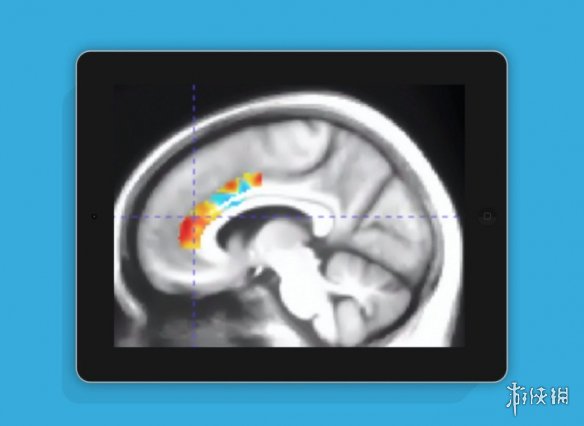

该研究由Mouna Attarha博士领导,成果已发表于题为《基于计算机认知训练对健康老年人大脑乙酰胆碱转运蛋白水平的影响》的学术论文中。作为“INHANCE”随机临床试验的一部分,研究团队招募了92名平均年龄为71.9岁、平均受教育时长为16.5年的健康老年人,进行了为期数月的系统测试。

研究结果令人振奋:参与者在完成10周的结构化认知游戏训练后,其大脑功能状态呈现出显著改善,认知表现平均“年轻化”了约十年。这一发现为通过非药物干预延缓老年认知退化提供了有力的科学依据。